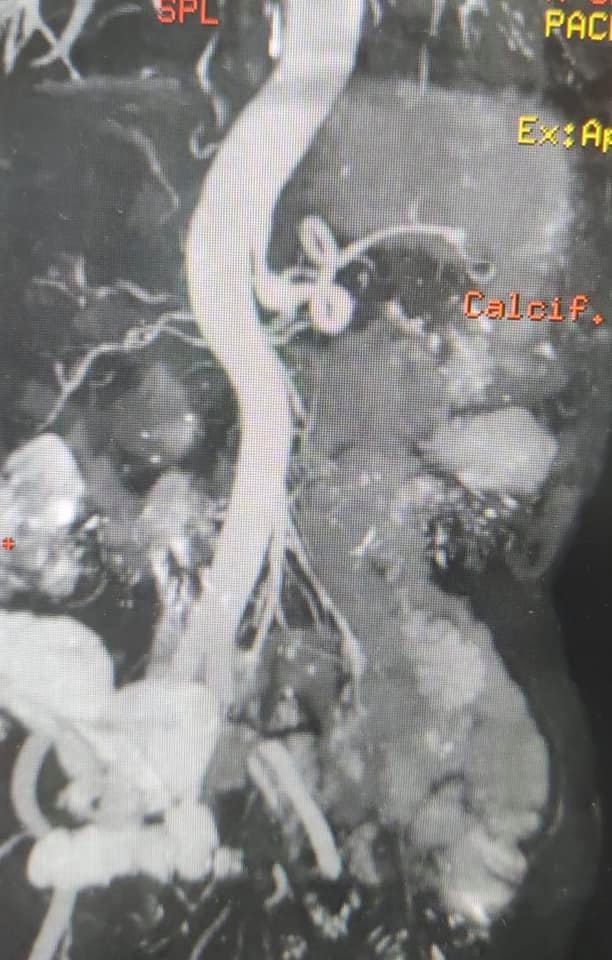

40 year old male with idiopathic chronic pancreatitis presented with intractable pain, sitophobia with severe weight loss (adult male weighs 29 Kg) and history of recurrent episodes of GI bleed. He also has CKD (cr1.7) related to neurogenic bladder. Patient was shifted to us in shock with HB 3 gm % and massive GI bleed. MRI and CT angio showed a large 6x5 cm Pseudoaneurysm in uncinate process of pancreas probably arising from inferior pancreaticoduordenal artery causing hemosuccus pancreas. In view of CKD we chose to tackle aneurysm by direct glue embolisation of aneurysm sac to avoid the high volume contrast of conventional angio (image) Pt was put on NJ feeds in view of severe malnutrition secondary to intractable pain and sitophobia. Post embolisation 2 months later he came back with weight gain of 8 kg and a stable Hb%. His Repeated CT scan showed a persistent intrapancreatic head cyst with dilated pd in body and tail. The aneurysm cavity filled with glue cast has shrunk to almost one fifth the initial size. In view of large duct disease with Pseudoaneurysm we decided to go ahead with a whipple pancreaticoduodenectomy. The post op specimen shows the intrapancreatic cyst and the glue cast of the aneurysm (yellow arrow). His recovery was uneventful and is completely pain free post procedure.